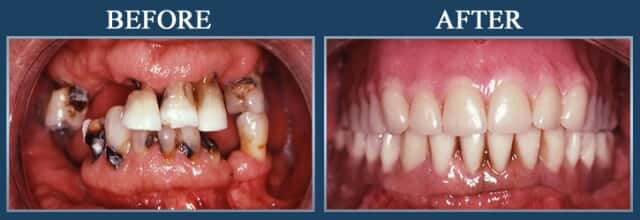

Gum Treatment